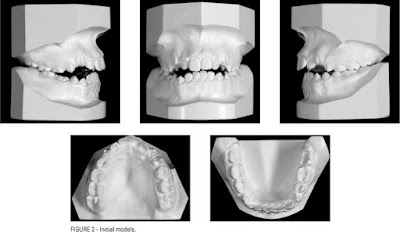

– Mẫu hàm thạch cao toàn diện trước và sau khi hoàn tất.

Nghiên cứu mẫu hàm sơ khởi